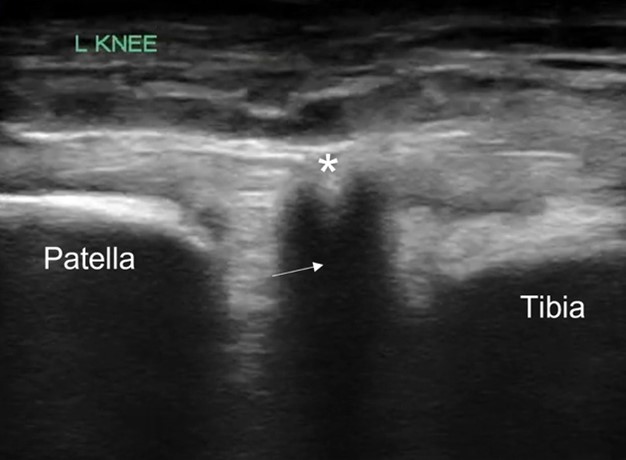

POCUS of the left knee was performed, which was concerning for a patellar tendon rupture and a joint effusion. (Figure 1 and Video 1) In addition, there was posterior acoustic shadowing obscuring part of the patellar tendon concerning for an avulsed bony fragment. (Figure 2) X-rays were performed, which confirmed the suspected diagnosis of a left tibial tubercle avulsion. (Figure 3) The patient was ultimately taken to the operating room for an Open Reduction and Internal Fixation (ORIF) by Orthopedic Surgery and discharged home the following day in a knee brace.

Figure 3. Lateral knee x-ray showing tibial tubercle avulsion (arrow)

In our case report, we successfully identified key features suggestive of tibial tubercle fractures: disruption of the patellar tendon, posterior acoustic shadowing of a bone fragment, and a large joint effusion. To perform knee ultrasound, the linear probe should be used and placed inferior to the patella in sagittal plane. The patellar tendon should be visualized in two planes, fanning through it completely (Video 1), and compared to the contralateral normal knee. (Figure 4) Abnormal findings suggestive of epiphyseal fractures include disruption of the tendon, an increased hypoechoic space adjacent to or posterior to the tendon (suggestive of either hemarthrosis or a hematoma), or a hypoechoic zone (ie, posterior acoustic shadowing due to an avulsed bony fragment).3,4